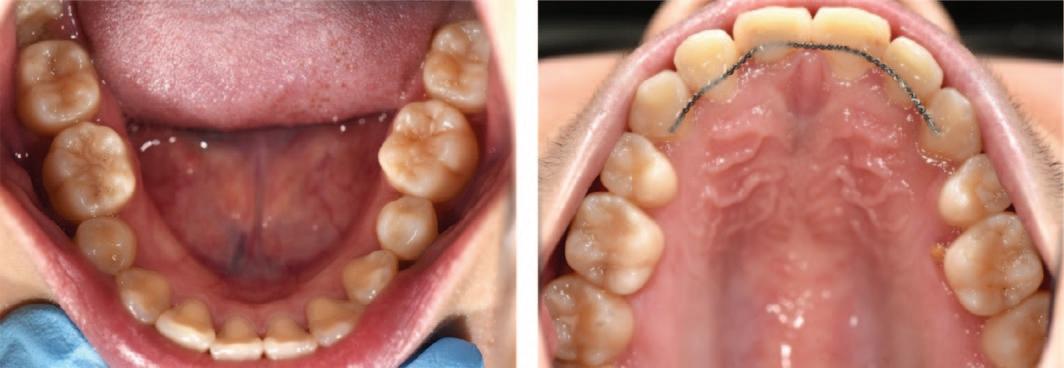

This patient first attended the Oral Surgery Department of Royal School of Dentistry Belfast for removal of a compound odontome in the right mandibular premolar region. This was an incidental finding discovered during assessment for orthodontic treatment (Figure 1). There was no evidence at that time of any other supernumerary teeth elsewhere in the jaws. This compound odontome tooth was surgically removed at that time following the informed consent process. The patient subsequently completed orthodontic treatment. Eight years later, at the age of 21, the patient was referred to the Oral Surgery Department for a second time due to the incidental finding of another supernumerary tooth on the contralateral side (Figure 2). The patient reported no relevant medical or genetic conditions. There was no reported family history

of supernumerary teeth. Clinical examination at age 21 years revealed a wellaligned dentition with a maxillary bonded retainer in place (Figure 2). No symptoms were reported related to the supernumerary teeth. None of the teeth were tender to percussion and all adjacent teeth exhibited a positive response to ethyl chloride. There was a palpable lingual bulge in the alveolar region of the lower left second premolar and first permanent molar. The panoramic radiograph indicated the presence of a radiopaque lesion and a radiolucent lesion in the left mandibular premolar region (Figure 3). A conebeam computed tomography scan was recorded to further characterise the lesion and surrounding area to aid surgical planning (Figure 4).